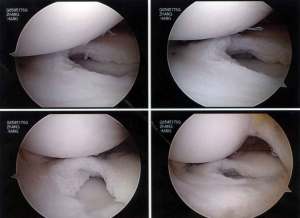

The discoid lateral meniscus was torn and detached from the capsule and has buckled into the inside of the joint. It looked like this:

Firstly the discoid portion of the lateral meniscus was removed arthroscopically as shown:

The final reconstructed discoid lateral meniscus looked like this: